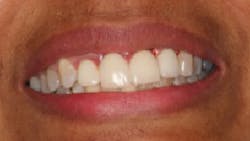

The patient was very pleased with the final outcome (figure 5), even though this case certainly would not be considered an esthetic success. Because of the patient’s concerns and low smile line (figure 6), this case was completed six months postextraction and in a cost-efficient manner.